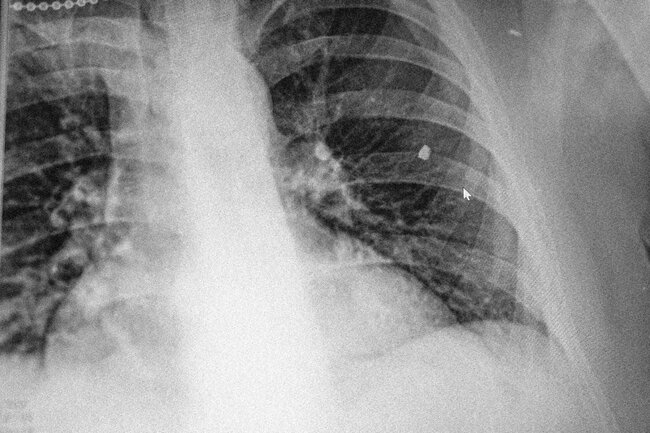

— Я начал кровью харкаться, говорю командиру: «Ты скинь на дроне парацетамол, я подлечуся». — «Не скину». Вечером вывезли, сделали снимок: «Так у тебя же воспаление легких, какой парацетамол».

— В легких тоже здоровый осколок. Полсиськи отрезали, ковыряли-ковыряли, ни хуя не достали, зашили — пиздуй. Врач сказал: «Тебя что-нибудь даже через броник сильно ударит — он влетит в легкие». Ну пока, видишь, живу на передке. Четыре контузии — в голове вообще ничего не держится, особенно цифры забываешь, шо капец.